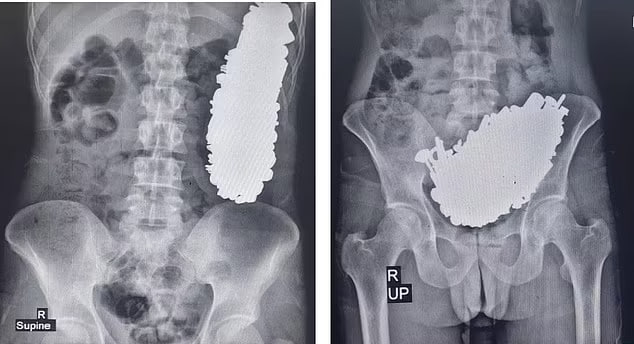

37-летний местный житель обратился в больницу Ахваза с жалобами на острые боли в животе и частую рвоту, из-за которых он не мог ни есть, ни пить. Обследование показало наличие большой массы металла в желудке иранца.

Проведена операция, в ходе которой из пациента извлекли почти 3 килограмма винтов, гаек, гвоздей, ключей, камней и прочей мелочи. Описывая случай, медики пришли к выводу, что такую богатую железом «диету» иранец соблюдал как минимум три месяца.